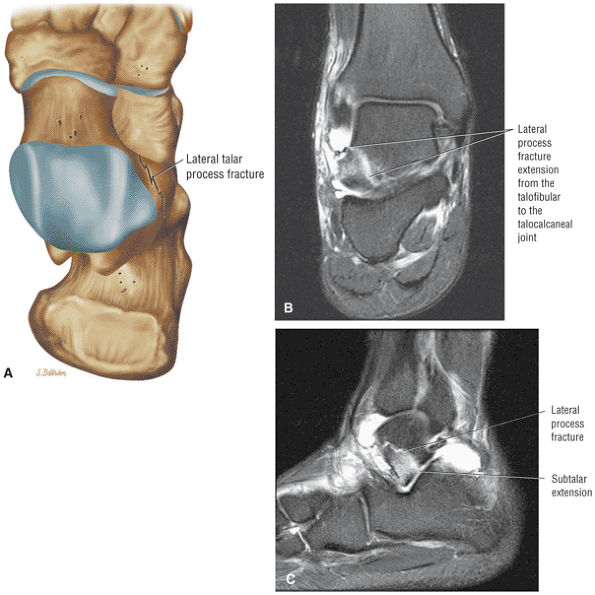

FIGURE 5.26 ● Coronal anatomy of the ankle and foot. (A) The calcaneofibular ligament (CFL) is identified by finding its origin at the inferior tip of the lateral malleolus. The posterior inferomedial course of the CFL is followed on three or four consecutive coronal images moving posteriorly through the ankle, to its insertion on the posterolateral calcaneus. Optimal evaluation of the CFL involves examining its full course on successive images in both the coronal and sagittal plane for tears, sprain, or scarring. (B) The medial cord of the plantar aponeurosis is normally slightly thicker than the lateral cord, and this mild asymmetry in thickness should not be misinterpreted as plantar aponeurosis scarring or plantar fasciitis. On successive coronal images, the course of the plantar aponeurosis should be followed back to its insertion on the inferior calcaneus and evaluated for the presence of thickening, decreased signal suggestive of scarring, increased signal indicative of plantar fasciitis, and tears. (C) Coronal images are optimal for viewing the lateral process of the talus, which is a frequent site of fractures that are occult on plain films. Fractures of the lateral process of the talus are most common in patients with snowboarding injuries. (D) The talar dome and tibial plafond are optimally visualized on coronal images. They are assessed for the presence of subchondral edema and cystic change with overlying chondral abnormalities. Close attention should be directed to the extreme anterior and posterior margins of the cartilage-bearing articular surfaces of the talar dome and tibial plafond to avoid overlooking osteochondral lesions at these locations. (E) The origin of the anterior talofibular ligament (ATFL) is found at the anterior distal tip of the lateral malleolus, and the ATFL is followed anteriorly on two or three successive coronal images to its insertion at the anterior lateral margin of the talus. (F) The deltoid ligament is optimally visualized in the coronal and axial planes. Tears of the deltoid manifest as loss of fiber striation or diffuse amorphous hyperintensity in the ligament on fluid-weighted sequences. Partial tears are more common than complete tears. (G) Focal fatty atrophy and denervation of the plantar flexor muscles of the foot (abductor digiti minimi, flexor digitorum brevis, and abductor hallucis) may indicate neuropathy involving the tibial nerve or its branches. (H) At the level of the anterior aspect of the talus and calcaneus, the peroneal tendons and flexor tendons turn from their cranial—caudal course to travel an anterior-to-posterior course along the plantar aspect of the foot. The distal portions of the tendons should be examined along the plantar aspect of the foot on successive coronal images for evidence of tendinosis and tears. (I) The base of the fifth metatarsal is a common location for fractures and is often visualized within the FOV on ankle MR exams. (J) At the level of the navicular, the flexor digitorum longus (FDL) and flexor hallucis longus (FHL) tendons run side by side, with the FDL medial to the FHL. Anterior to this level on successive coronal images, the two tendons cross, with the FHL medial to the FDL as the FHL courses to its insertion on the great toe. (K) Stress fractures of the navicular are commonly vertical in the midline of the navicular, an appearance that is well characterized on coronal images. (L) Contusions, stress-related edema, fractures, and degenerative arthritis of the midfoot bones and joints are common causes of midfoot pain and are often optimally identified on fluid-sensitive sequences.